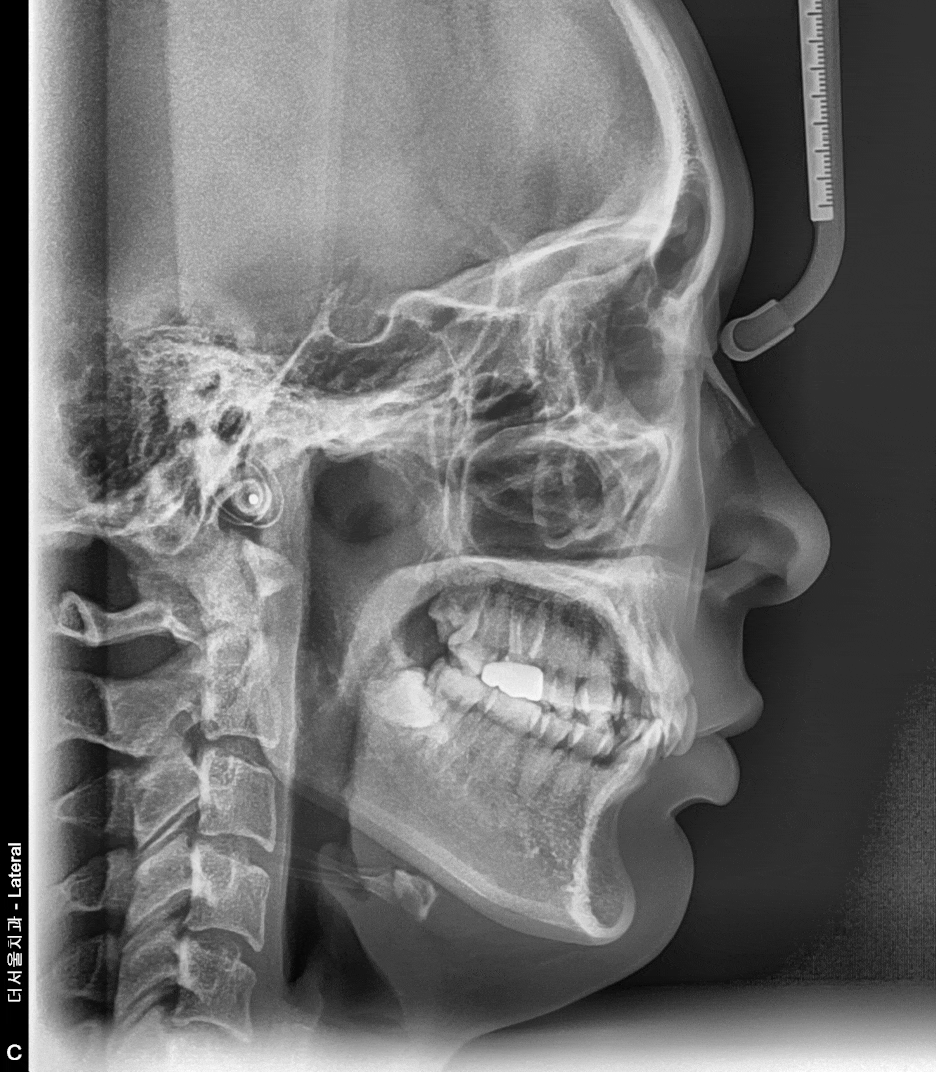

게다가, 측면 Ceph 사진을 봤을 땐

앞니가 그렇게 뻐드러져 있는 느낌은

받을 수 없습니다.